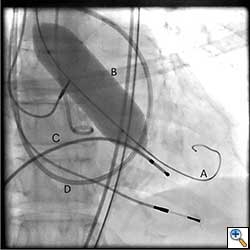

A cut-down is then performed in the ipsilateral groin and the femoral artery is exposed. Using a 18 gauge needle, wire access is achieved in the femoral artery using Seldinger technique. A 14 Fr sheath is then placed in the femoral artery. Using a straight wire through an AL1 guide catheter (Boston Scientific Corporation, Massachusetts), the stenotic aortic valve is crossed and images are obtained to assess the left ventricular outflow tract, the native aortic valve and its relation to the coronary ostia. The AL1 guide catheter is then advanced into the left ventricle and the straight wire is then exchanged for a stiff wire such as an Extra-stiff Amplatz (Cook Medical, Indiana) or Lunderquist guidewire (Cook Medical, Indiana). Next, a balloon aortic valvuloplasty (BAV) is performed with the use of a Tyshak 22 mm balloon (B. Braun Medical Inc., Pennsylvania) to facilitate crossing of the native stenotic valve with the Edwards Sapien valve (Figure 1). BAV is performed during a short period of rapid ventricular pacing to minimize transvalvular flow and potential embolization. It is critical to stabilize hemodynamics after the valvuloplasty due to hypotension from rapid pacing and from the ensuing aortic insufficiency.